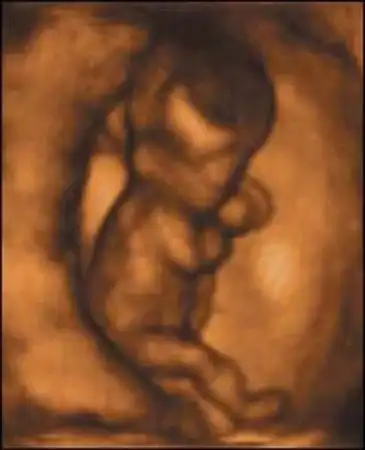

Британские ученые засняли на пленку поведение плода на самых ранних стадиях беременности. Оказывается, зародыш начинает двигаться уже в возрасте 12 недель, вслушивается в голос матери и плачет, когда будущая мама курит...

Уникальная ультразвуковая аппаратура, при помощи которой были получены эти видеозаписи, позволяет не только получать всевозможные фотографии плода, но и наблюдать за ним в реальном времени...

Книга профессора потрясла ученых. В частности, в ней ученый утверждает, что ребенок шевелится уже в 12 недель, задолго до того, как мать начинает ощущать его движения...

Маленький человечек умеет спать...

С 9-й недели начинается плодный период. Особенно интенсивно развивается печень. До 20-й недели она играет роль главного кроветворного органа ребенка. Активно растут мышцы на руках и ногах. Плод в состоянии двигаться, но пока хаотично, поскольку мозжечок еще не созрел.

На 11-й неделе продолжается окостенение скелета. Развиваются эндокринные железы и лимфоузлы. Сердце бьется с частотой 130-150 ударов в минуту. 9-сантиметровый ребенок двигает головой, руками, ногами, сжимает кулачки, поворачивает голову и даже пробует сосать свой палец.